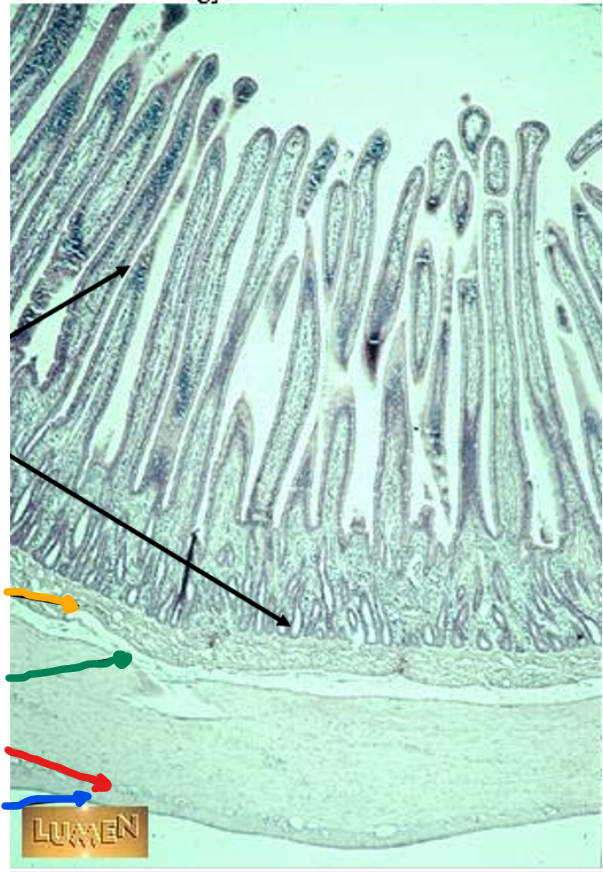

plicae circulares

green

villi

crypts

blue

lamina propria

black

simple columnar epithelium

black arrows

mucosa

yellow arrow

submucosa

red arrows

muscularis externa

blue arrow

serosa

this is in the

jejunum